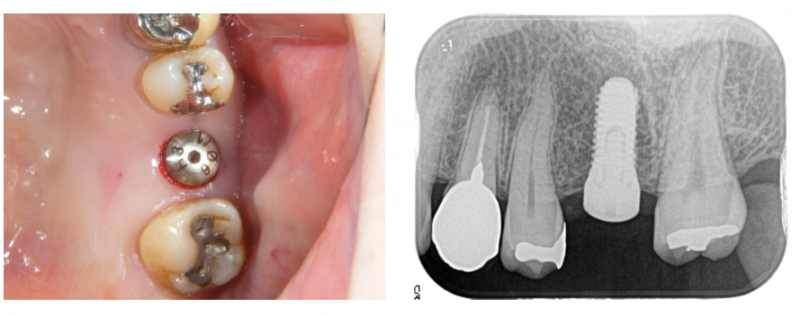

術前診査

口腔内診査、レントゲン、CTなどから骨量は十分と判断し、

歯肉を開かず(フラップレス)埋め込みすることにしました。

インプラント埋め込み

埋め込み直後の写真です。歯肉を開いていないので、出血もほとんど無く縫合もしていません。

1本の埋め込みなら15分程度で終了します。麻酔は、普通の歯科治療のものを使います。この状態で、3ヶ月ほど待ちます。

写真は、鏡の上にのせて撮っています。